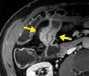

Souhrn: Úvod: Zobrazovací metody mají v diagnostice pacientů s Crohnovou chorobou nezastupitelnou úlohu. V současné době existuje několik skórovacích systémů, jejichž cílem je pomocí předem stanovených parametrů objektivizovat hodnocení zánětlivého postižení střeva. Cílem této práce bylo srovnání nálezu zánětlivého střevního postižení na koloskopii a magnetické rezonanci (MR) při použití skórovacího systému MaRIA. Materiály a metody: Pacienti s Crohnovou chorobou podstoupili v rozmezí do 2 měsíců koloskopii a MR enterografii ve Fakultní nemocnici Brno v letech 2020–2022. Aktivita onemocnění na koloskopii byla hodnocena pomocí SES-CD a Rutgeerts score, na MR pomocí MaRIA skóre (zesílení stěny, její sycení, edém a přítomnost ulcerací). Nálezy z obou zobrazovacích metod byly srovnány, koloskopie byla zvolena zlatým standardem. U každého pacienta bylo analyzováno terminální ileum, tlusté střevo (rozdělené anatomicky na čtyři segmenty) a rektum. Výsledky: V této retrospektivní studii bylo analyzováno 203 střevních segmentů u 43 po sobě jdoucích pacientů (42 % mužů). Senzitivita MR enterografie v hodnocení aktivity střevního zánětu byla 62 %, specificita 94 %. Všechny parametry určující aktivitu zánětu na MR byly signifikantně vyšší u pacientů s aktivitou dle koloskopie a celková hodnota MaRIA skóre byla rovněž vyšší v této skupině (12,76 ± 7,48 vs. 5,27 ± 3,45; p < 0,001). Senzitivita se zvýšila na 90 % při izolované analýze tenkého střeva, při analýze tlustého střeva se naopak snížila na 34 %. Závěr: V naší studii jsme prokázali shodu mezi MR s použitím MaRIA skórovacího systému a koloskopií při hodnocení střevního zánětu u pacientů s Crohnovou chorobou. Klí ová slova: magnetická rezonance – koloskopie – Crohnova choroba – MaRIA